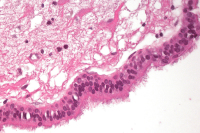

Fallbericht: Blickdiagnose "Arachnoidalzyste" erweist sich als Irrtum: akute Symptomatik einer 14 Jahre alten supratentoriellen endodermalen Zyste

Journal für Neurologie, Neurochirurgie und Psychiatrie 2015; 16 (4): 178-182 Volltext (PDF) Praxisrelevanz Abbildungen